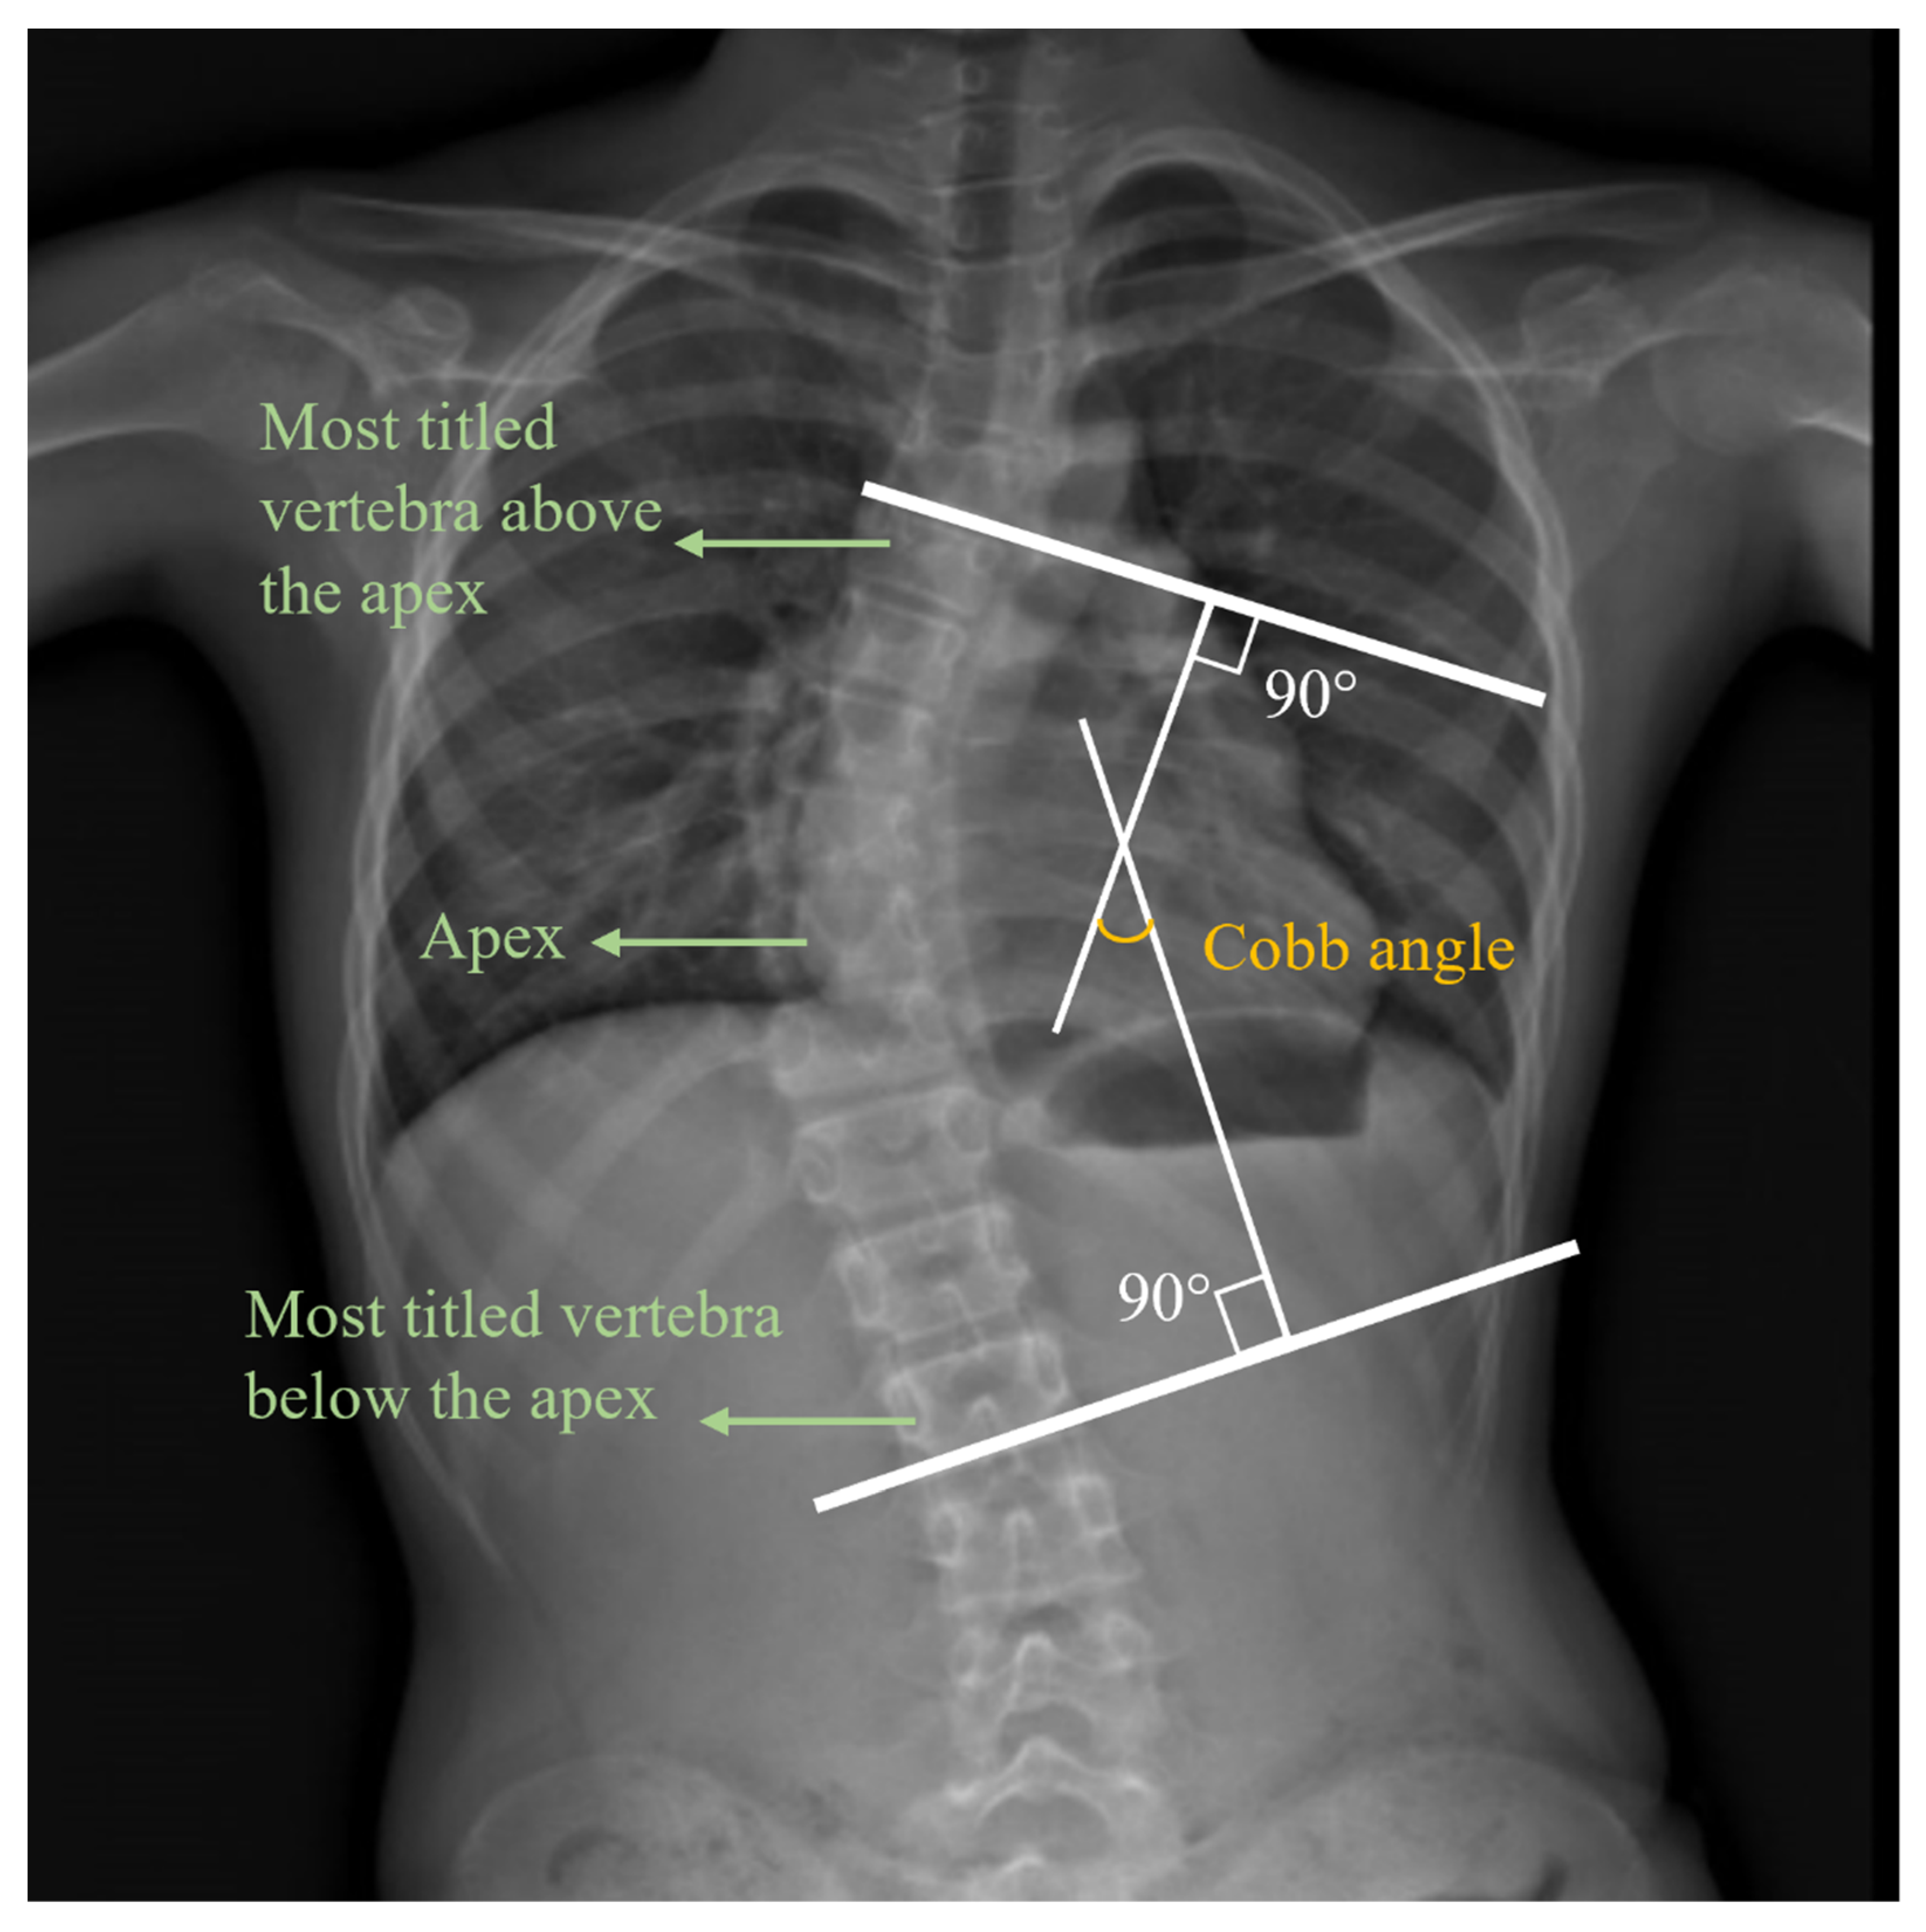

- Horng, M.-H.; Kuok, C.-P.; Fu, M.-J.; Lin, C.-J.; Sun, Y.-N. Cobb Angle Measurement of Spine from X-Ray Images Using Convolutional Neural Network. Comput. Math. Methods Med. 2019, 2019, 6357171. [Google Scholar] [CrossRef] [Green Version]

- Greiner, K.A. Adolescent idiopathic scoliosis: Radiologic decision-making. Am. Fam. Physician 2002, 65, 1817–1822. [Google Scholar]